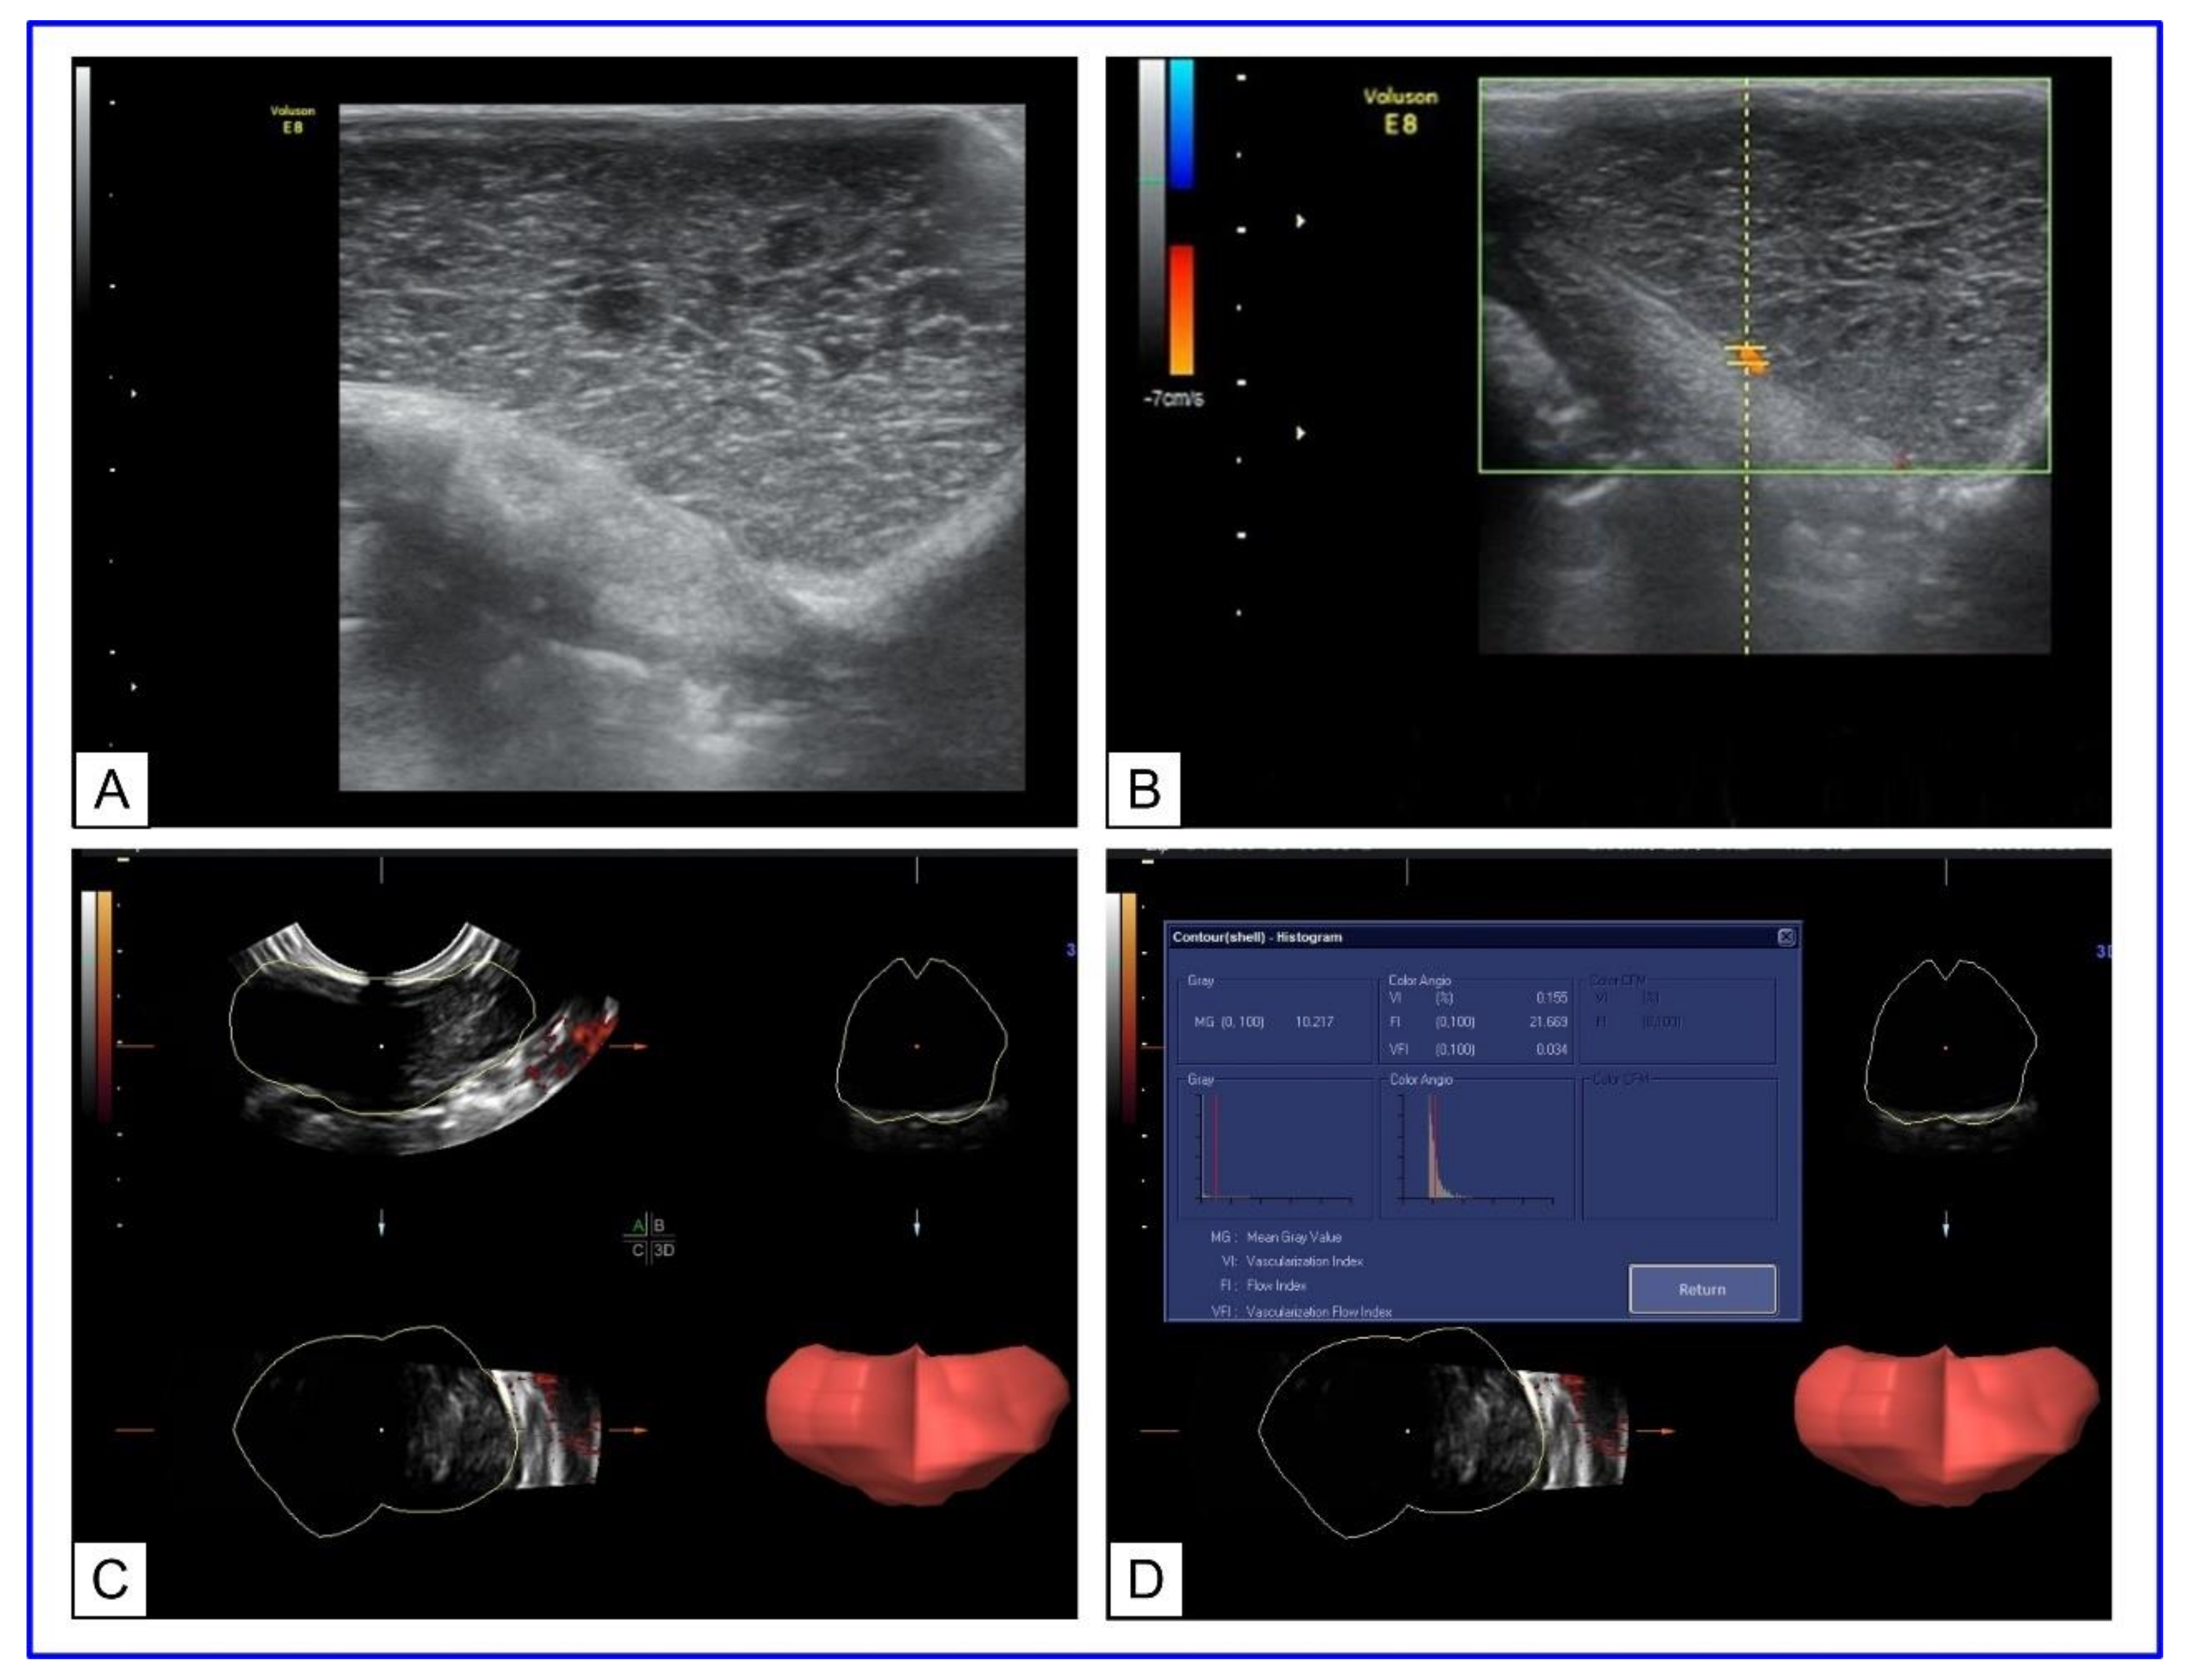

- Bucharskaya, A.B.; Maslyakova, G.N.; Chekhonatskaya, M.L.; Terentyuk, G.S.; Navolokin, N.A.; Khlebtsov, B.N.; Khlebtsov, N.G.; Bashkatov, A.N.; Genina, E.A.; Tuchin, V.V. Plasmonic Photothermal Therapy: Approaches to Advanced Strategy. Lasers Surg. Med. 2018, 50, 1025–1033. [Google Scholar] [CrossRef]